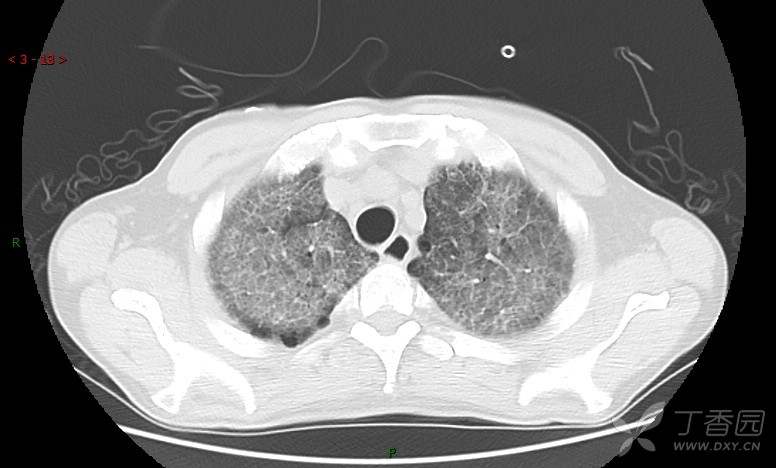

地图+铺路石征=PAP?那升高的CEA怎么说(病例3连发,附其他2例链接)

患者男,42岁,咳嗽半年余,加重伴憋喘2月余。

血清肿瘤相关抗原116.22U/ml↑(0--95);

癌胚抗原 61.96 ng/mL ↑ 0--5

神经特异性烯醇化酶 33.12 ng/ml ↑ 0--16.3

细胞角蛋白19片段测定 40.23 ng/ml ↑ ≤3.3

肺内弥漫性网状结节影,PET-CT却无阳性病灶,这是?(附其他2例链接)